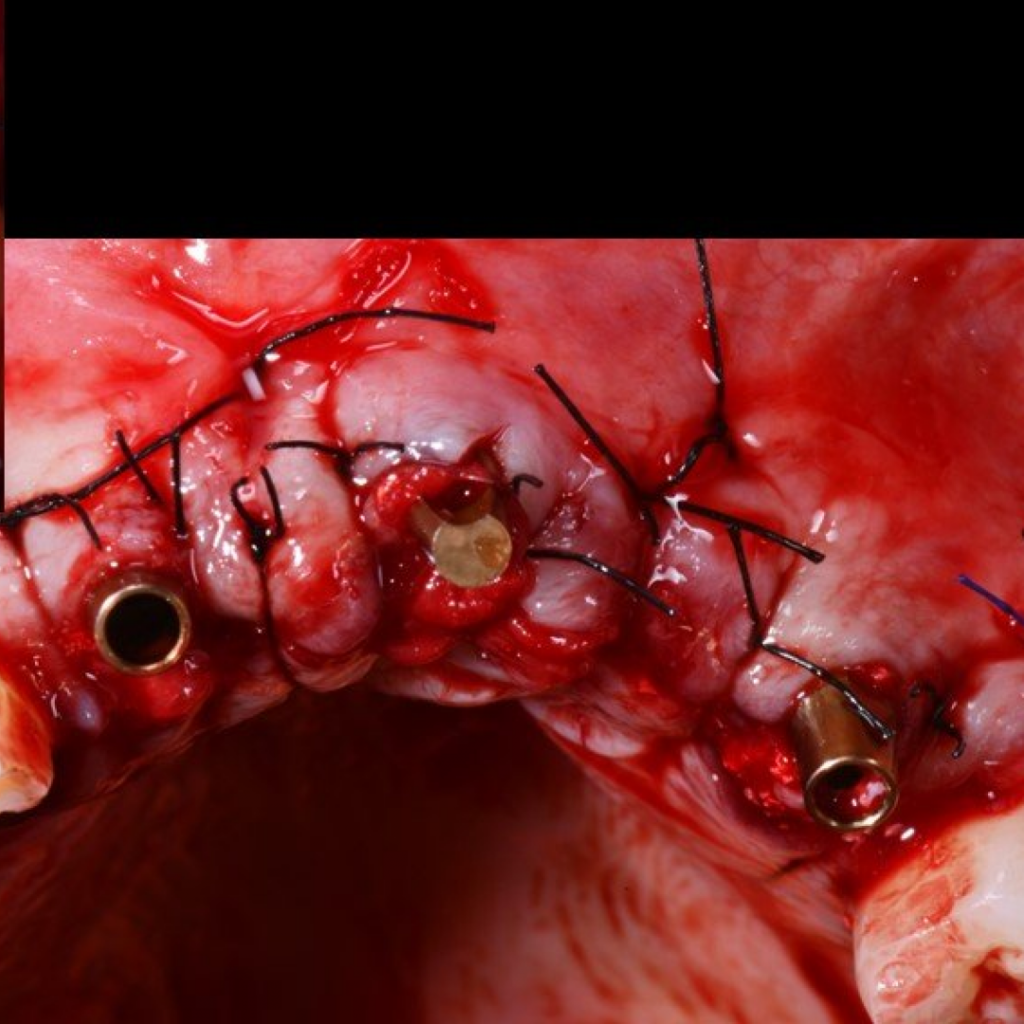

- Заполнение костных дефектов смесью из костного материала TI-oss, аутокости пациента и обогащенной тромбоцитами плазмой PRP

- Установка абатментов для временного протеза

- Покрытие зоны аугментации коллагеновой мембраной